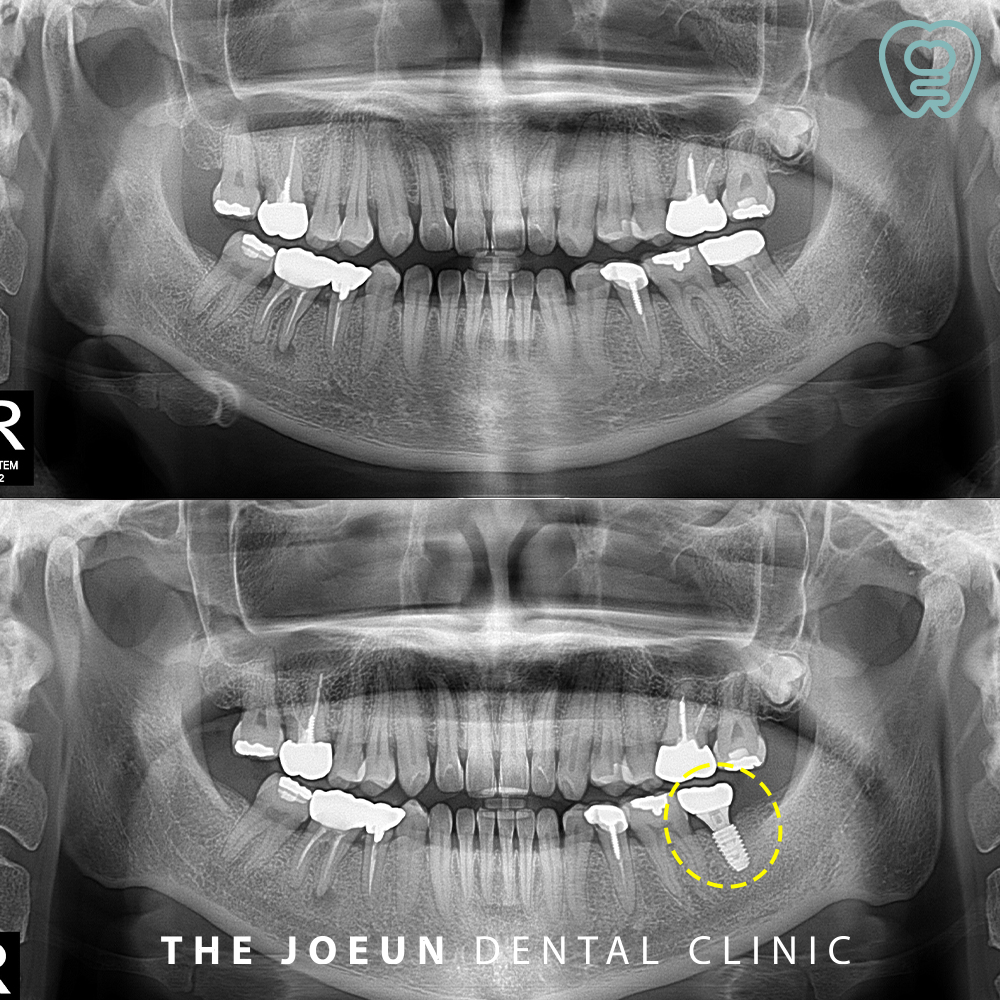

오늘은 신경관과 가까이 있는 치아 뿌리의 염증으로 인해 발치 후 충분한 기간을 기다려준 뒤 임플란트를 식립하신 환자분을 소개해 드리도록 하겠습니다. 환자분께서는 전체적인 검진을 위해 내원하셔서 왼쪽으로 식사를 하실 때 간혹 찝찝한 느낌은 있었지만 큰 불편함은 없으셨다는 말씀을 해주셨는데요.

파노라마를 확인해보니 왼쪽 아래 신경치료 후 크라운이 되어 있는 가장 안쪽 어금니의 뿌리에 커다란 염증이 발견되었습니다. 문제는 뿌리의 염증이 아래쪽의 신경관과 매우 가까워 보였는데요.

당일 발치를 먼저 진행하였습니다.

충분히 잇몸뼈가 차오를 수 있도록 약 3개월 후 임플란트 식립을 진행하였는데요.

인공치근을 식립하고 3개월 뒤 최종 보철물까지 완성한 모습입니다.